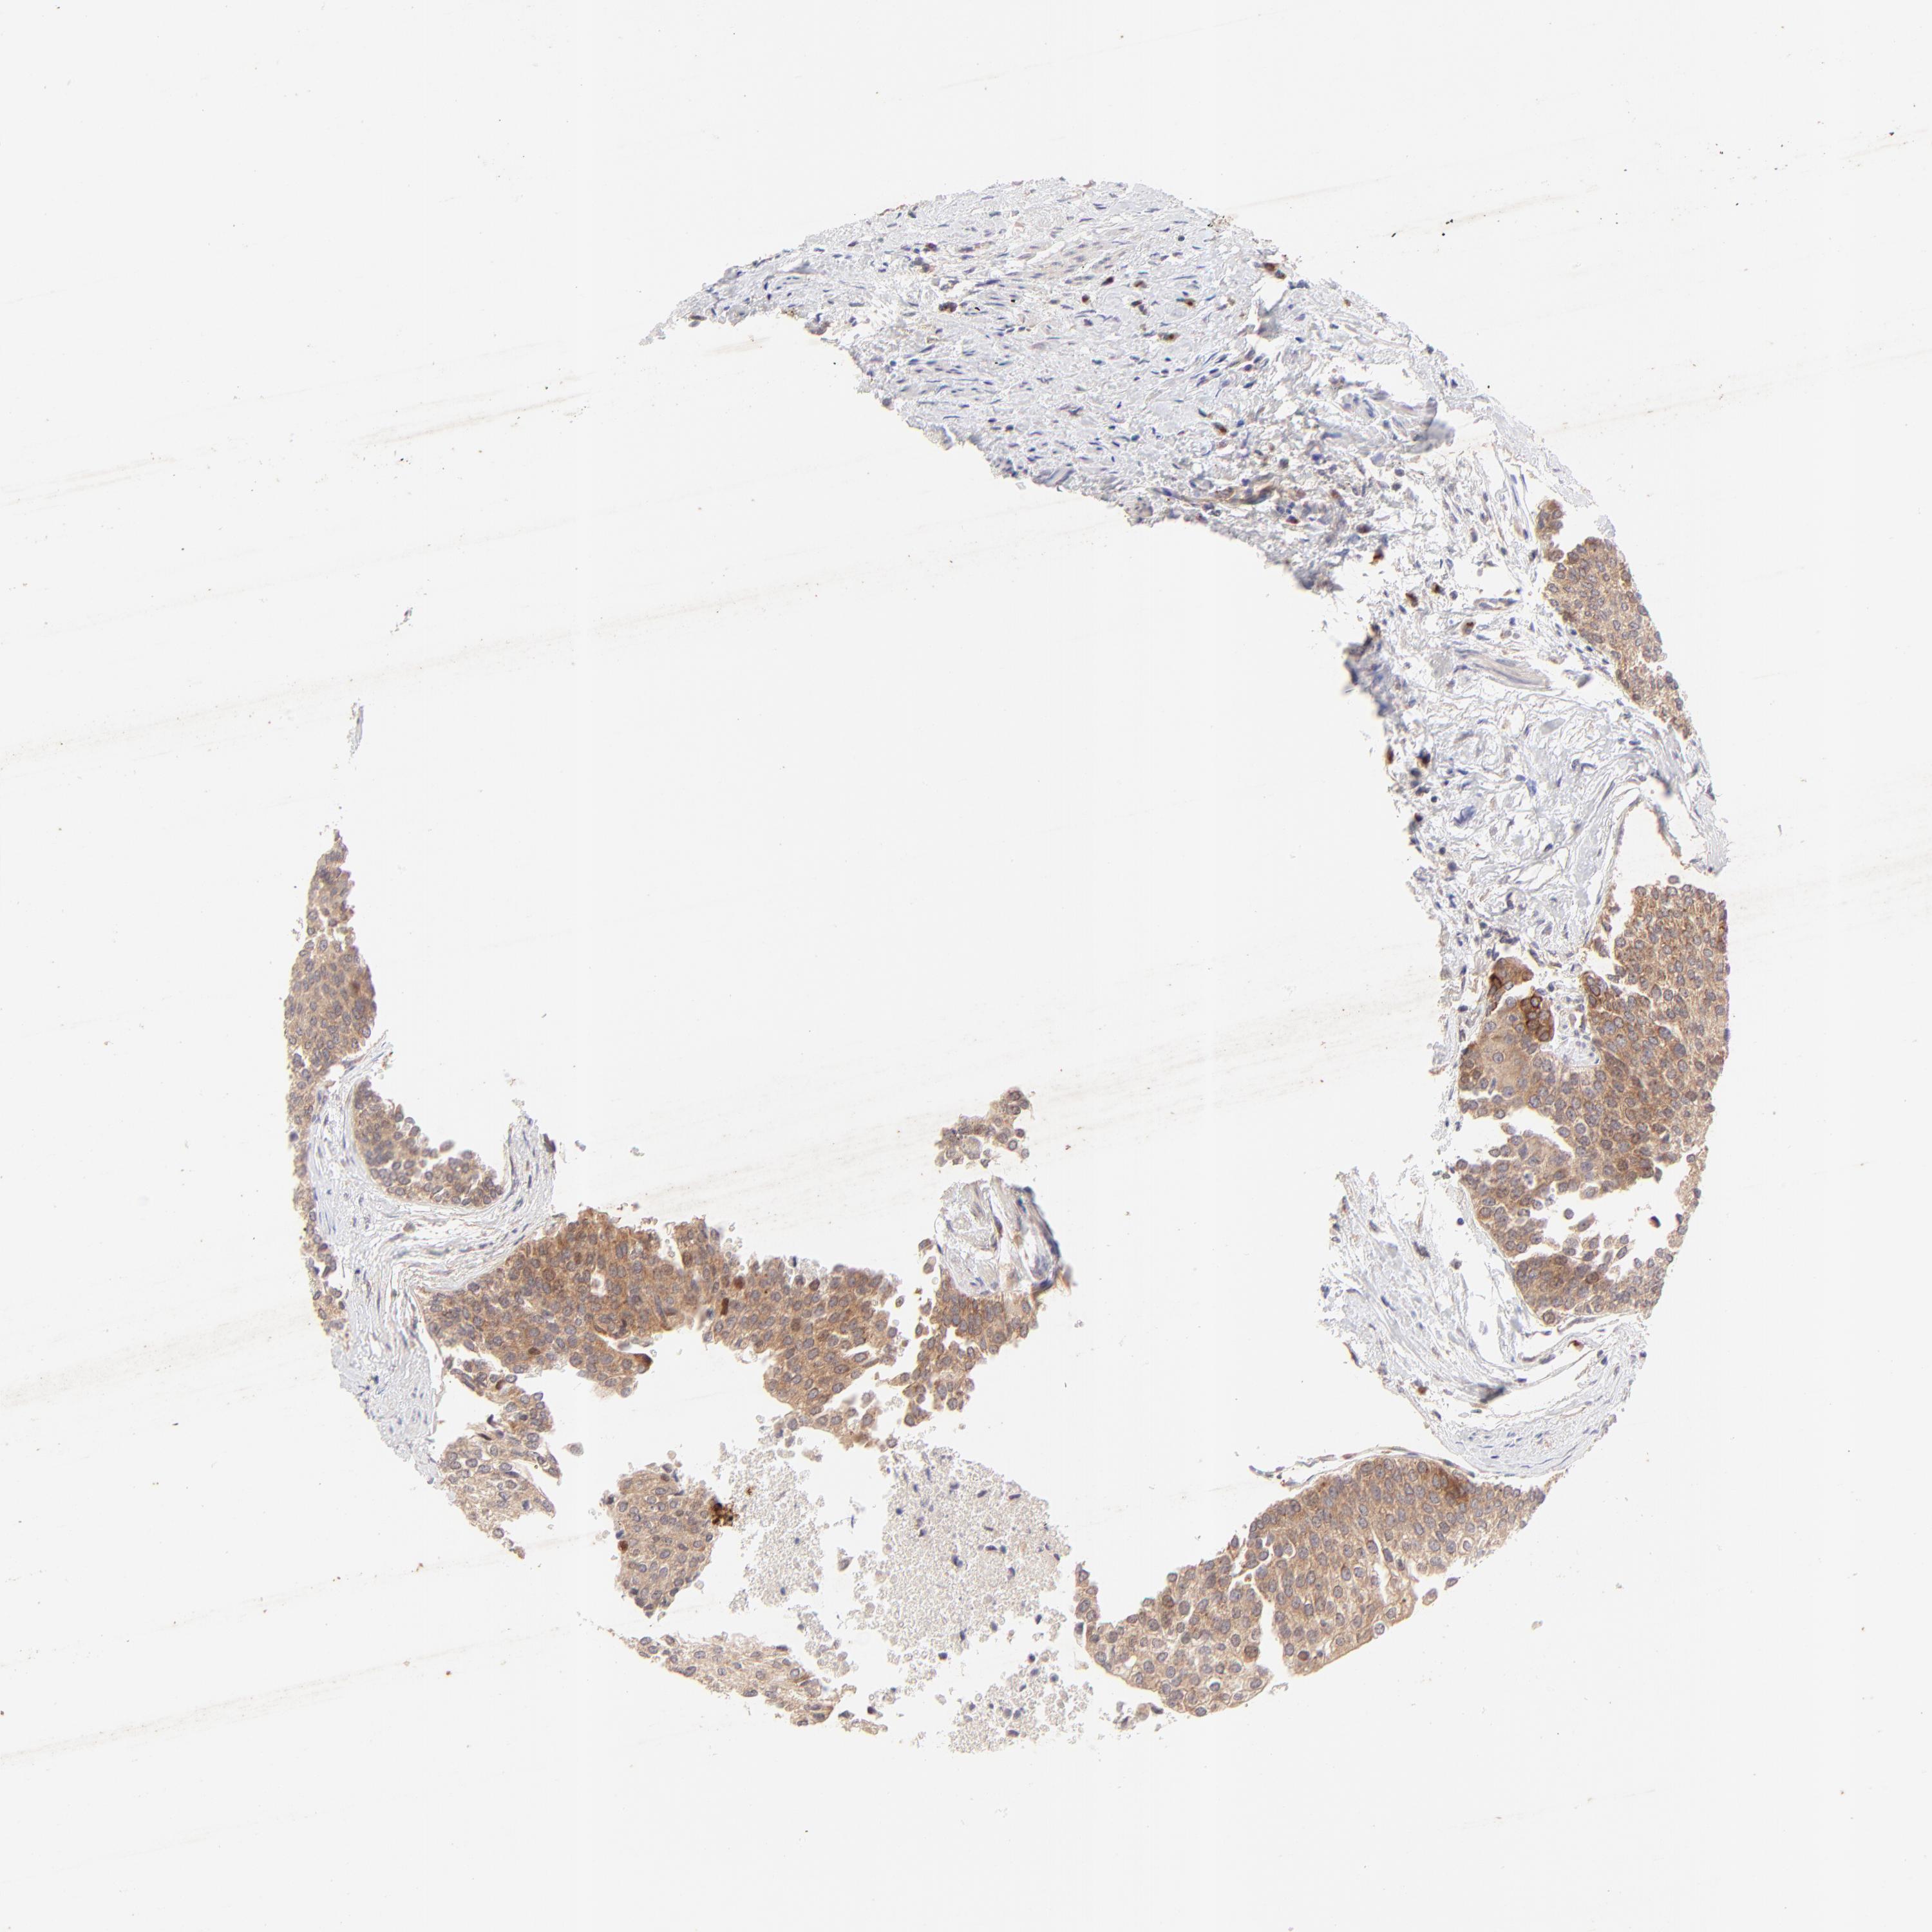

UROTHELIAL CANCER - Protein expressioni

A mouse-over function shows sample information and annotation data. Click on an image to view it in a full screen mode. Samples can be filtered based on level of antibody staining by selecting one or several of the following categories: high, medium, low and not detected. The assay and annotation is described here.

Note that samples used for immunohistochemistry by the Human Protein Atlas do not correspond to samples in the TCGA dataset.

Antibody stainingi

Antibody staining in the annotated cell types in the current human tissue is reported as not detected, low, medium, or high, based on conventional immunohistochemistry profiling in selected tissues. This score is based on the combination of the staining intensity and fraction of stained cells.

Each image is clickable and will lead to virtual microscopy that enables deeper exploration of all samples and also displays staining intensity scores, fraction scores and subcellular localization as well as patient and tissue information for each sample.

Antibody HPA003180

Staining

High

Medium

Low

Not detected

Intensity

Strong

Moderate

Weak

Negative

Quantity

>75%

75%-25%

<25%

None

Location

Nuclear

Cytoplasmic/membranous

Cytoplasmic/membranous,nuclear

Urothelial carcinoma, High grade

Urothelial carcinoma, Low grade